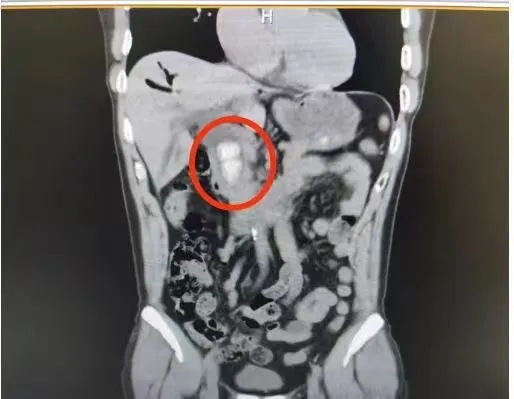

日前,我院内镜室应用经口胆管镜+液电碎石术,成功完成一例胆总管取石术。患者李伯,因为腹痛、发烧入院,经检查发现2个大小约2.5*3.0CM的胆总管巨大结石,由于十年前做过胆囊切除术,给他带来了很大的心理负担,老人家对开刀手术十分抗拒,希望可以通过微创治疗解决问题。

石胜利主任医师了解情况后,随即组织科内医生进行讨论,考虑到李伯胆总管处的结石较大,取出难度高。结合实际情况,决定使用目前最先进的经口胆道镜+液电碎石术,为李伯取出胆总管内的巨大结石。最终,医护人员在胆道镜直视状态下清晰观察到李伯的胆总管结石,并通过液电设备将结石精准击碎,然后顺利取出。